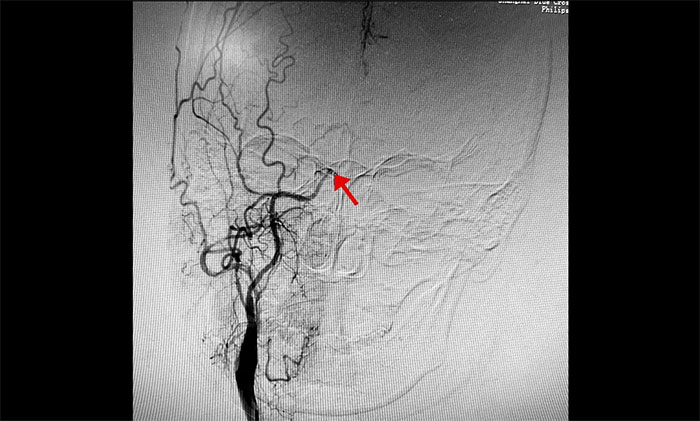

于耀宇主任為患者行DSA(數(shù)字減影血管造影)檢查示:右側(cè)頸內(nèi)動(dòng)脈末端閉塞,大腦中動(dòng)脈M1段、大腦前動(dòng)脈A1段不顯影。左側(cè)頸內(nèi)動(dòng)脈、大腦前動(dòng)脈亦存在不同程度狹窄。顱底可見少量煙霧狀血管形成,符合煙霧病特征。

▲ 右側(cè)頸內(nèi)動(dòng)脈末端閉塞,少量煙霧狀代償血管形成